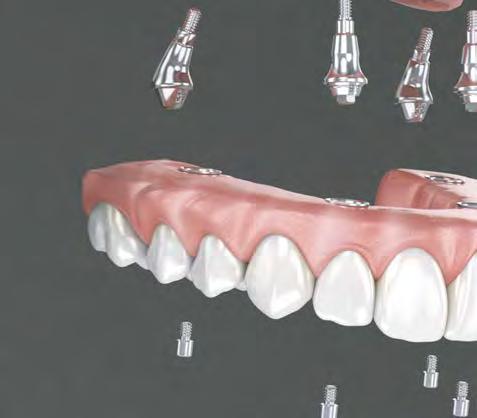

Protocolo Di gitalArch®️ 2.0: técnica de colocación, por el Dr. Luis Cuadrado Canals y cols.

SUSCRIPCIONES Y DISTRIBUCIÓN

Remedios García

Laura López suscripciones@peldano.com 902 35 40 45

BUSINESS UNIT MANAGER

Miguel Ángel Cañizares miguelangel@gacetadental.com